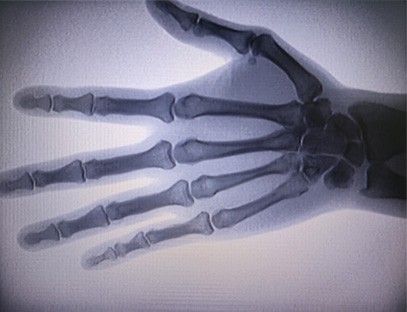

インスタントイメージングポータブルX線装置整形外科クリニック向けに特別に設計された、四肢のX線撮影を行う医療機器です。X線の透過性と人体のさまざまな組織間のX線吸収レベルの違いを利用して、内部構造情報を視覚画像に変換し、医師の診断と治療を支援します。特に、個人クリニック、獣医、ペット病院に適しています。四肢撮影X線装置は、ペット医療で使用され、獣医師の病気の診断と治療を支援します。

ポータブルX線装置は、放射線量が低く、非常に安全なポータブル機器であり、放射線被ばくを減らしながら高品質の画像を取得できます。 大型病院機器の欠点を補い、いつでも移動して持ち運ぶことができます。 特に、予算が不十分で画像に対する要件が低いユニットや個人に適しています。 当社の新世代X線装置は、10インチの高解像度大画面を備えており、視野角範囲が広く、骨折、脱臼、関節炎、骨腫瘍など、手のひら全体を完全に見ることができます。 フィルムプリンターに接続して整形外科用フィルムを印刷できるほか、工業生産やテストにも使用できます。 暗室は不要、直接視点、リアルタイム観察。 このマシンには高解像度の画像システムがあり、あらゆる骨構造の画像を非常に鮮明にキャプチャできます。 医療、ペット、工業、電子製品メーカー、検査・保守部門、研究室に最適なX線検査装置とソリューションを提供します。

専門分野:整形外科クリニックのニーズに合わせて設計されており、特にX線画像手、手首、肘、肩、膝、足首などの手足。

鮮明な画像:高度なデジタル画像技術を使用して高品質のX線画像を提供し、医師が病状を正確に診断するのに役立ちます。